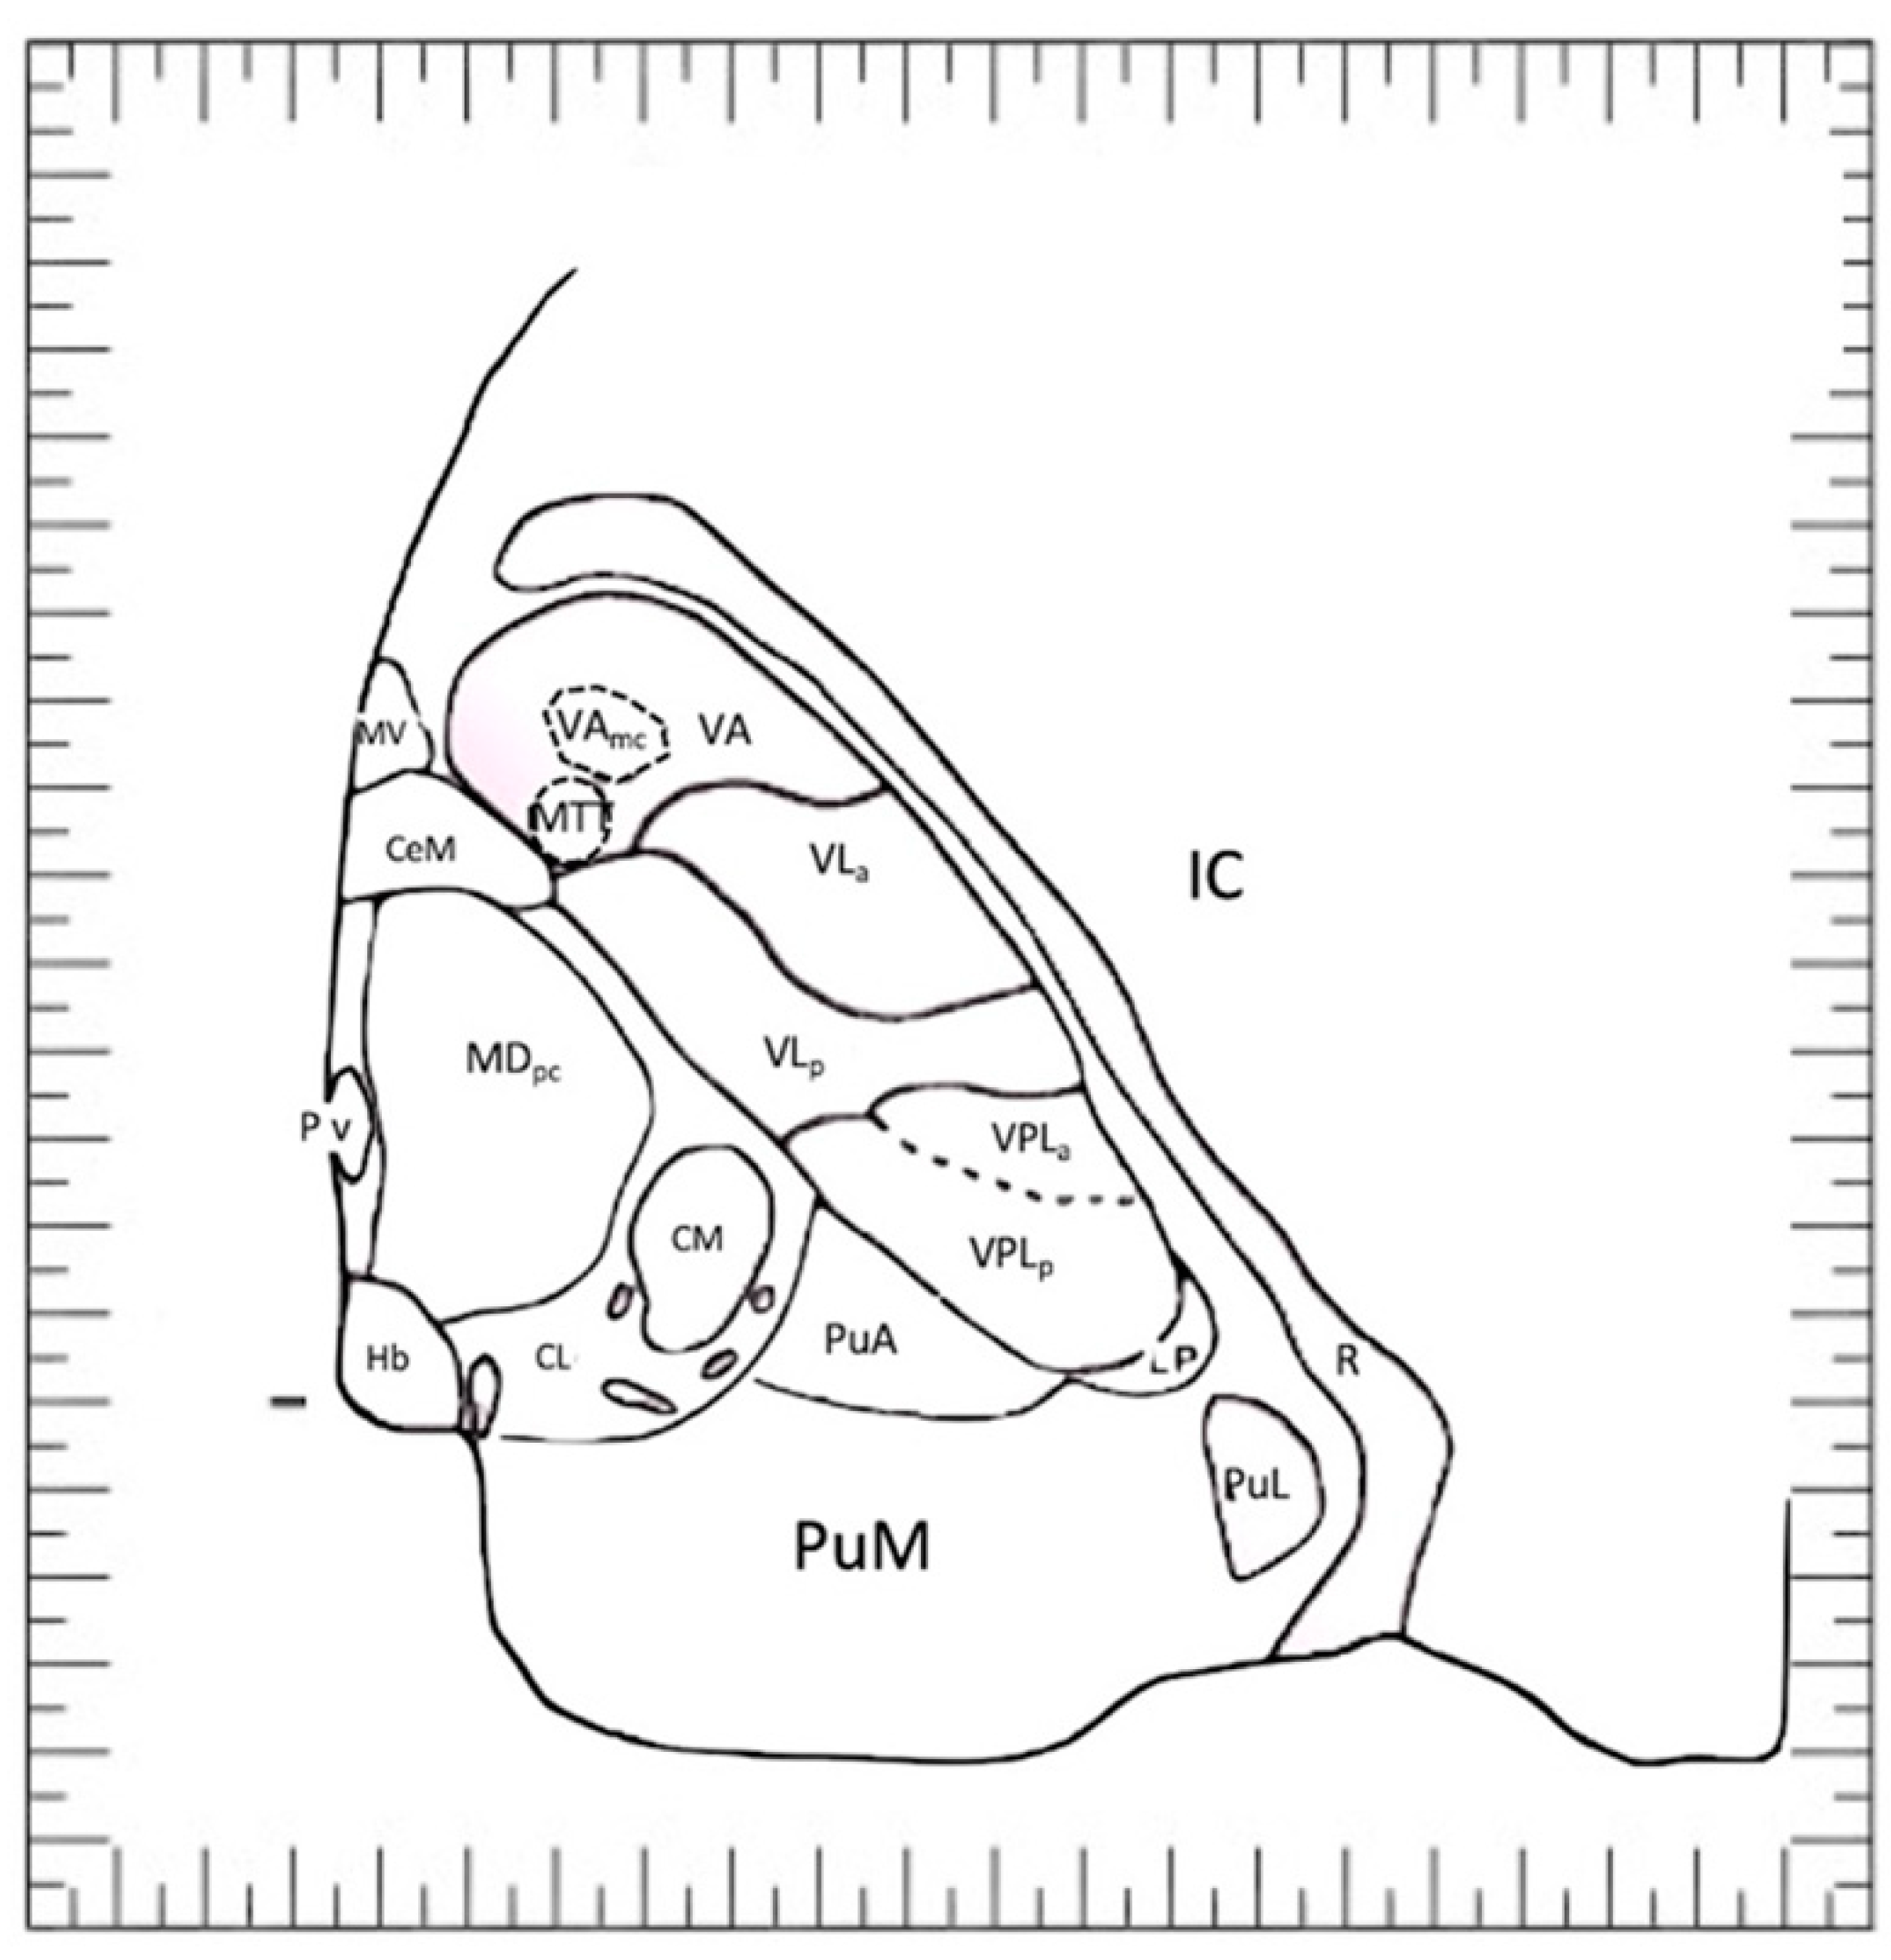

6. An Atlas Showing Variations in Human Diencephalon